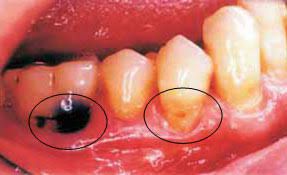

Poor oral hygiene and decreased in salivary flow (dry mouth) are the risk factors of root caries. Dry mouth is usually related to medications, and is not age related. The colour of the decay varies depending on the amount of the decay present and where on the tooth the decay is located.